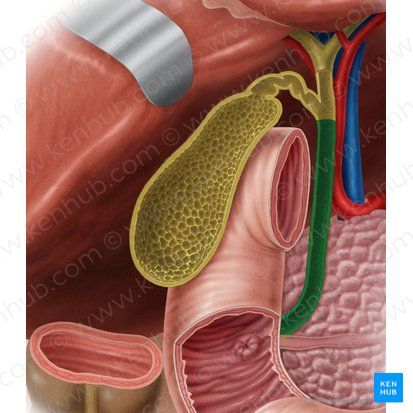

Gallbladder

A small, pear-shaped organ located beneath the liver that stores and concentrates bile produced by the liver.

Right Hepatic Duct

A duct that carries bile produced by the right lobe of the liver.

Left Hepatic Duct

A duct that carries bile produced by the left lobe of the liver.

Common Hepatic Duct

The duct formed by the union of the right and left hepatic ducts, which carries bile away from the liver.

Cystic Duct

The duct that connects the gallbladder to the common hepatic duct, allowing bile to enter and exit the gallbladder.

Hepatic Artery

A branch of the celiac artery that supplies oxygenated blood to the liver.

Hepatic Portal Vein

A large vein that carries deoxygenated but nutrient-rich blood from the digestive organs (stomach, intestines, spleen, pancreas) to the liver for processing.

Inferior Vena Cava

A large vein that carries deoxygenated blood from the lower and middle body back to the heart.

Pancreatic Duct

A duct that carries digestive enzymes produced by the pancreas to the duodenum. It typically joins with the bile duct before entering the duodenum.

Bile duct

A duct that carries bile produced by the liver and stored in the gallbladder to the duodenum, where it aids in the digestion of fats.